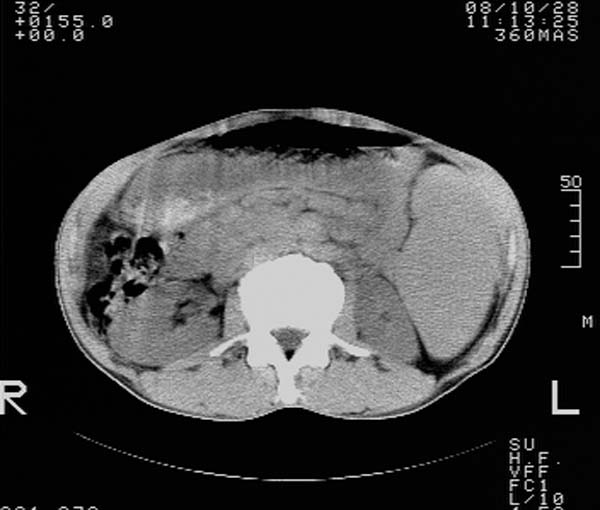

m,65y。半年前发现颈小结节,逐渐增多增大,现双侧耳后、颌下及颈部表浅淋巴肿大。胸片示双肺门增大。外院曾穿刺诊断为淋巴结核。在我科作胸腹部ct,我们觉得外院病检有误。现将图像上传请战友讨论。

纵隔内及腹膜后广泛淋巴结肿大,脾大,肝内似可见低密度影,结合病史半年前发现颈小结节,逐渐增多增大,现双侧耳后、颌下及颈部表浅淋巴肿大。考虑淋巴瘤。

我们也是首先考虑淋巴瘤。只是外院病检报告是结核。让人迷惑。肝左叶多发低密度占位,没增强不好定论。

纵隔,双肺门腹膜后多发淋巴结重大,非融合,肝脾轻度肿大,双肺野弥漫性小结节;考虑淋巴瘤,结节病可能性

纵隔内,双肺门、腋窝及腹膜后多发肿大淋巴结影,肺内小结节影,肝脾体积增大,支持淋巴瘤。肝内多发低密度影,考虑小囊肿。

考虑淋巴瘤肺、肝内转移,脾脏肿大。

纵隔内,双肺门、腹膜后多发肿大淋巴结影及颈部淋巴结肿大,肝脾体积大.结合临床,淋巴瘤可能性大。